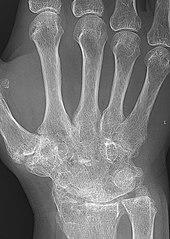

X-ray of the wrist of a woman with rheumatoid arthritis, showing unaffected carpal bones in the left image, and ankylosing fusion of the carpal bones 8 years later in the right image.

The disease progresses by forming granulation tissue at the edges of the synovial lining, pannus with extensive angiogenesis and enzymes causing tissue damage.[54] The fibroblast-like synoviocytes have a prominent role in these pathogenic processes.[19] The synovium thickens, cartilage and underlying bone disintegrate, and the joint deteriorates, with raised calprotectin levels serving as a biomarker of these events.[55]

X-rays of the hands and feet are generally performed when many joints affected. In RA, there may be no changes in the early stages of the disease or the x-ray may show osteopenia near the joint, soft tissue swelling, and a smaller than normal joint space. As the disease advances, there may be bony erosions and subluxation. Other medical imaging techniques such as magnetic resonance imaging (MRI) and ultrasound are also used in RA.[22][58]